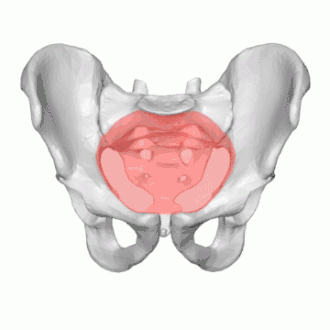

![]() Diameters of superior aperture of lesser pelvis (female) | |

The diameters or conjugates of the pelvis are measured at the pelvic inlet and outlet and as oblique diameters.

Name | Description | Average measurement in female |

Anteroposterior or conjugate diameter or conjugata vera | Extends from the upper margin of the pubic symphysis to the sacrococcygeal joint; | about 110 mm. |

Transverse diameter | Extends across the greatest width of the superior aperture, from the middle of the brim on one side to the same point on the opposite; | about 135 mm. |

Oblique diameter | Extends from the iliopectineal eminence of one side to the sacroiliac articulation of the opposite side; | about 125 mm. |

Anatomical conjugate | Extends from the pubic symphysis to the promontory; | about 120 mm. |

Diagonal conjugate | Extends from lower margin of the pubic symphysis to the sacral promontory; | about 130 mm. |

Straight conjugate | Extends from the lower border of the pubic symphysis to the tip of coccyx. The coccyx can bend posteriorly and expand the diameter with 25 mm; | about 95 mm (+ 25 mm). |

Median conjugate | Extends from the lower border of the pubic symphysis to the lower border of the sacrum; | about 115 mm. |